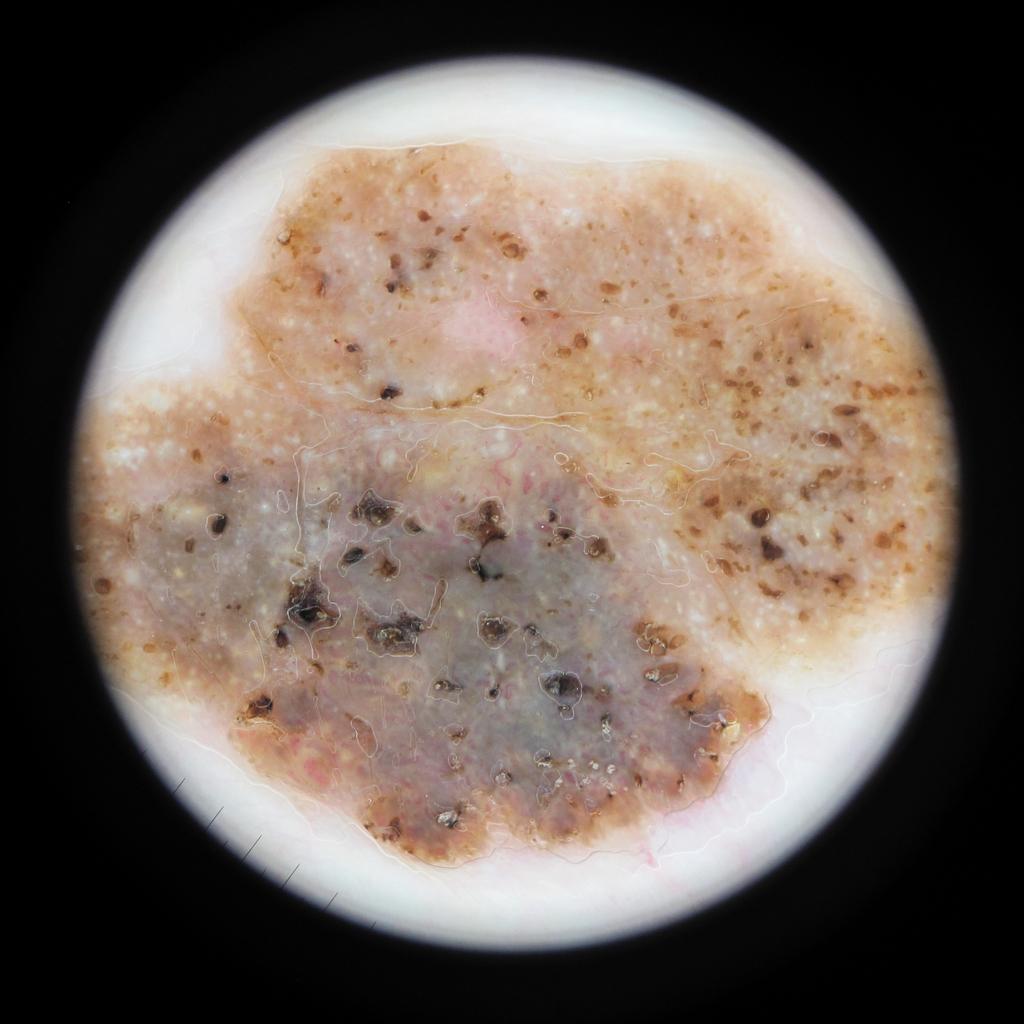

Case: 50